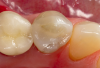

Transilluminating technologies emit light at the base of the tooth at the gingival area and transmit light up through the tooth. At the applied wavelength, enamel starts to absorb fewer photons and water starts to absorb more photons, so lesions appear as dark areas on a monitor.6-8 This visualization can be helpful not only for the clinician to identify and diagnose problematic areas (Figure 1), but it also allows patients to see all aspects of their mouth including their cheek, tongue, and tooth, as well as the areas that have decay, thereby potentially assisting in case acceptance.

Transillumination can be used in interproximal, occlusal, and anterior surfaces.5 In many cases the technology is able to show how expansive the decayed area is on occlusal areas that may only have a minimal pit that would not allow a probe to be used (Figure 2 through Figure 4). Visualizing the interproximal regions of posterior teeth is possible as well although this may require a specialized fiber-optic tip.6